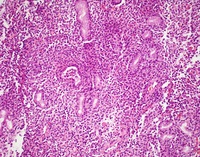

Gastric body biopsies HE

Biopsies of the gastric body shows a diffuse infiltrate of bland monotonous small lymphoid cells with moderate amount of pink cytoplasm and bland nuclei percolating in the lamina propria without any destructive features.